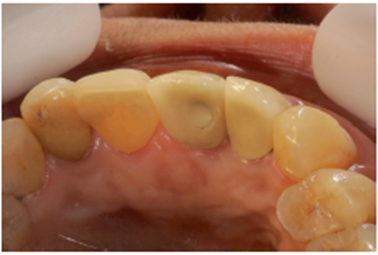

Paciente A.N., sexo feminino, 54 anos, procurou a clínica odontológica com fistula na região do elemento 11 (Figura 1). Foi solicitada tomografia computadorizada Cone Beam da região (Figura 2). Ao exame tomográfico foi diagnosticada a lesão periapical extensa, com perda óssea, envolvendo o elemento 11 (Figura 3). O plano de tratamento proposto foi a exodontia do elemento 11, curetagem da lesão e instalação imediata de um implante Cone Morse, juntamente com o procedimento de ROG, fazendo uso de biomaterial de origem bovina (Bio-Oss 0,25) e membrana de PTFE-d (Cytoplast TXT–200, Osteogenics – Lubbock TX, EUA) no mesmo momento cirúrgico.

No laboratório, o técnico de prótese posicionou o pilar Ideale angulado no modelo (Figura 27) e confeccionou um incisivo central parafusado sobre ele, utilizando a coifa de provisório que o sistema oferece (Figura 28). Uma vez obtido o provisório, o cicatrizador voltou a ser removido e o pilar Ideale e o provisório foram instalados em boca (Figuras 30 e 31). O pilar foi torqueado em 20 Ncm e o parafuso da coroa foi torqueado em 10 Ncm. Após 15 dias, o provisório foi removido e observou-se o perfeito perfil de emergência que havia sido obtido (Figura 33). Neste novo momento foi posicionado sobre o pilar um transferente plástico de moldeira fechada do pilar Ideale, sendo que tanto o pilar como o dente 12 foram moldados (Figura 34) para a confecção de copings e posterior a aplicação da cerâmica (Figura 35).

Após a conclusão desses passos pelo laboratório, a prótese do elemento 12 foi cimentada com fosfato de zinco e a prótese sobre o pilar Ideale foi parafusada e torqueada a 10 Ncm (Figura 36). O orifício de acesso foi restaurado com resina fotopolimerizável (Figura 37). Uma radiografia final foi realizada, demonstrando o perfeito assentamento da coroa sobre o pilar Ideale.